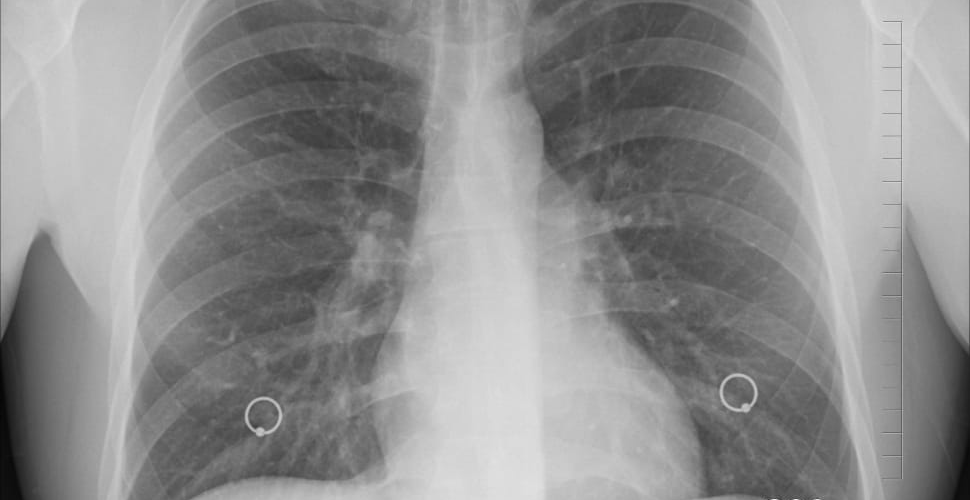

Peakpx › human lung xray

アイキャッチ画像:Peakpx > human lung xray